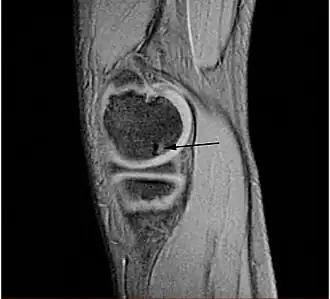

Osteocondritis disecante

![]() Lesión típica de osteocondritis disecante en la cabeza del fémur, causada por una necrosis avascular del tejido subcondral. | ||

Osteocondritis disecante (a menudo abreviado TOC o DO) es un trastorno común en el que se forman grietas en el cartílago articular y el hueso subyacente subcondral. El TOC es una complicación de la necrosis avascular que se producen en el hueso subcondral.[1] Esta necrosis avascular priva de sangre a los huesos; el tejido afectado muere y se reabsorbe. El hueso subcondral se pierde, el cartílago articular anterior se separa del hueso y es más propenso a los daños, como la fragmentación (disección) de los cartílagos y huesos, y la libre circulación de estos fragmentos osteocondrales en el espacio articular, causando más dolor y daño.[2][3][4]